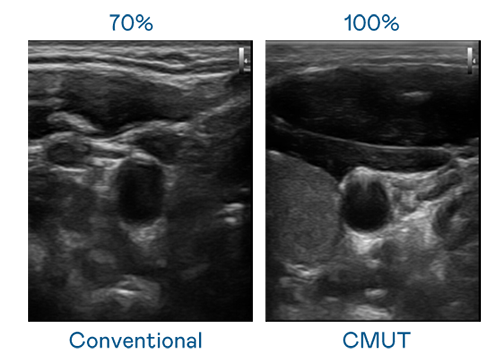

CMUT 技术是一种用电容式微机电元件来产生超音波讯号的技术。与传统 PZT 压电式技术相比,CMUT 频宽增加 30%,更宽频的超音波讯号让影像解析度大幅提升,是实现高影像品质医疗超音波扫描、促进精准医疗发展的关键技术。

超音波影像的解析度高低,首先取决于探头能发出的讯号频宽。尊龙凯时人生就搏 CMUT 可提供高清晰的超音波讯号,提供高频宽、高灵敏度、影像纹理细节更高的超音波影像,协助医护人员缩短影像判读时间及利用精准的医疗影像进行诊断。